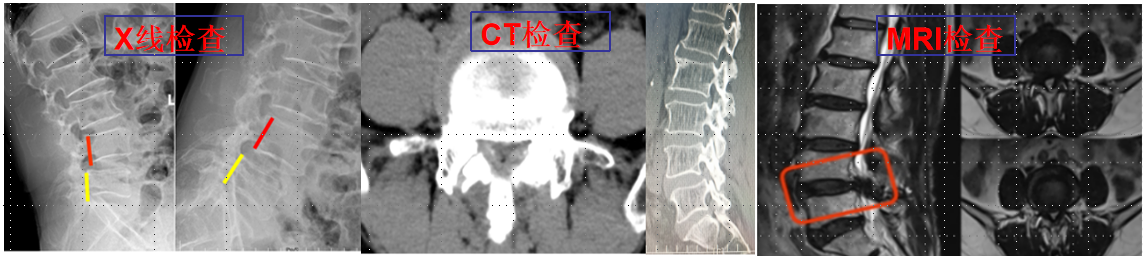

UBE(Unilateral Biportal Endscopic,单侧双通道内镜技术)是新兴的一种脊柱外科微创技术,被广泛应用于脊柱退行性疾病(包括腰椎间盘突出症、腰椎滑脱、腰椎管狭窄、颈椎病等)的治疗,收到了较好的临床效果。UBE手术具有视野清晰、创伤小、出血少、效率高、疗效好及恢复快的特点。我院在重庆市较早开展此项技术,多次通过手术直播、学术讲座和实操培训形式充分展示此项技术。

94f27ffa5ca14b1f82cb4ee9d26b4a66.Png

4f400e6adfaa40aa970dedaf1200326f.Png

椎间孔镜技术:

利用椎间孔镜从患者腰椎侧方或者后方进入达到椎间盘突出或者其他病变部位,用专用工具将突出(脱出)的椎间盘组织或病变取出(去除)从而达到治疗椎间盘突出或者椎管狭窄的目的。它的优势在于:局部麻醉、微创、切口小(仅约7mm)出血少,恢复快(第二天即可佩戴硬腰围下地)及疗效好。

539650c2baae42ea976bd4bf6a4f7947.Png